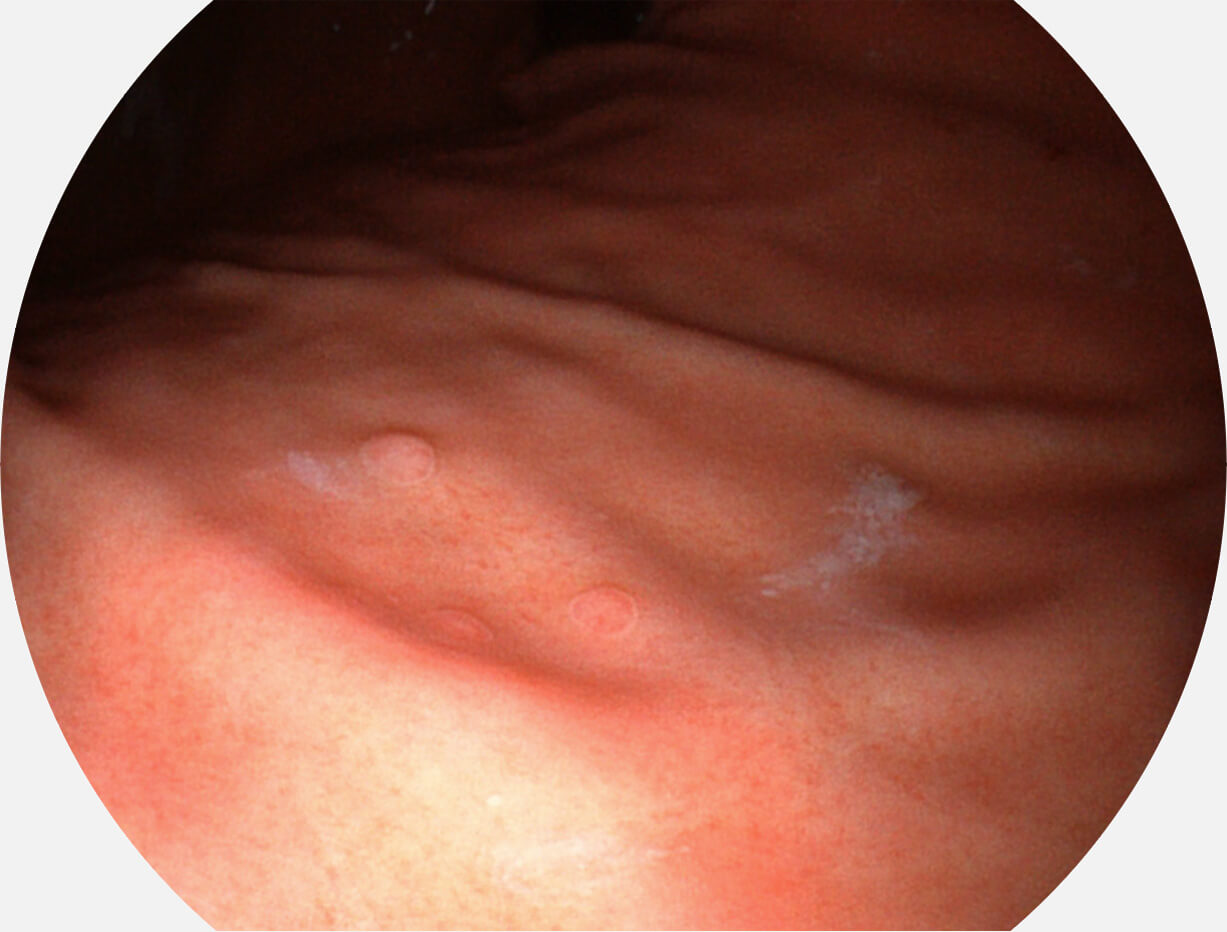

SFI图像

图像具有高亮度、高黏膜血管颜色对比度的特点,且不改变粘液、食物残渣、粪便的基本颜色,可在中远景下进行观察,助力消化道早期疾病的诊断。